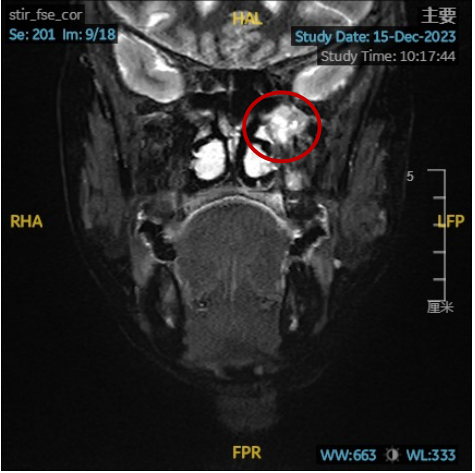

周女士,今年50多岁,3个月前她突然感觉左侧面部胀痛,反复出现,有时咳痰还带血,症状越来越严重……周女士和家人非常着急,来到昆山市一医院耳鼻咽喉头颈外科就诊,门诊医生通过鼻内镜观察到,周女士的左侧下鼻道内有红色肿物!通过增强CT检查显示:红色肿物来源于左侧后鼻腔及左侧翼腭窝,肿物病理结果:腺样囊性癌,医院安排周女士入院治疗。

丁小军团队在鼻内镜术中发现:肿物向前下方附着于前颅底,翼管神经、上颌神经和腭大神经已贯穿入肿瘤内部,情况非常复杂和艰难!历时三个半小时,终于从颅底骨质**肿物和肿物所侵犯的神经全部分离和切除。术后磁共振检查显示:肿物完全切除,翼内肌、翼外肌安全保留。